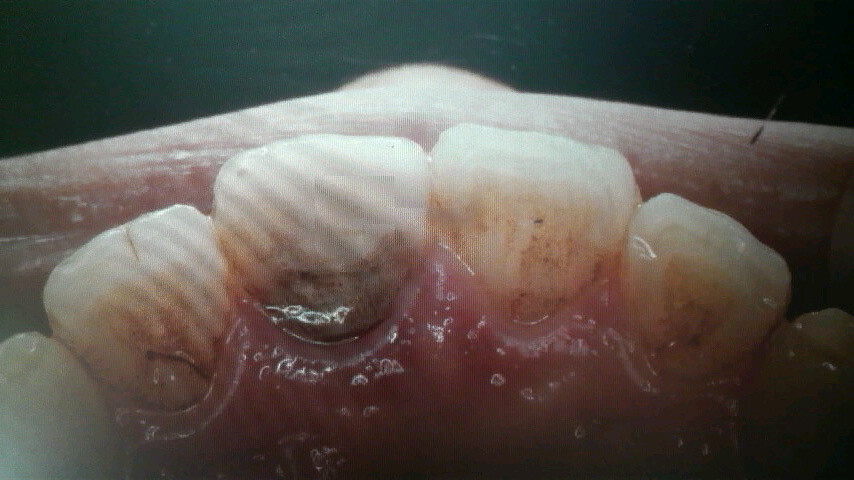

成人矯正症例 A.M

4番を抜歯して前歯をリトラクションして歯列を改善した症例です。